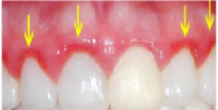

주로 잇몸병은 초기에는 일시적으로 양치할 때 잇몸이 붓고 피가 나는 증상이 나타납니다. 또 음식을 씹을 때 치아가 아파요 하고 병원을 찾으시는 분들도 계시는데, 잇몸이 부어도 식사할 때 치아가 아픈 것처럼 느껴질 수 있습니다. 치경부에 한해서 생긴 초기 잇몸병, 즉 치은염이라고 하는데요, 주로 양치가 잘 안돼서 많이 나타나고 때로는 피로함, 호르몬에 의해 나타날 수도 있습니다. 주로 치아와 잇몸 경계부가 붓고 피가 나게 됩니다.

치은염은 스케일링받고 평소에도 치실이나 치간칫솔로 구강 내 환경을 깨끗하게 유지시켜 주면 금방 나을 수 있습니다.